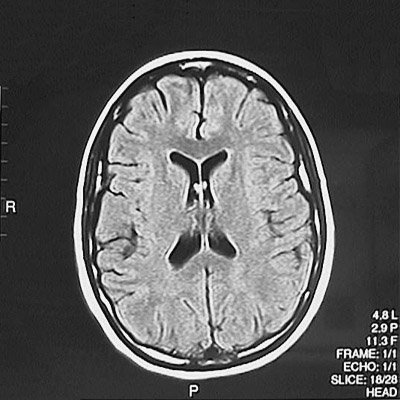

This is a normal axial T1 weighted MRI scan demonstrating the frontal lobe and parietal lobe and genu of corpus callosum and splenium of corpus callosum and anterior horn of lateral ventricle and posterior horn of lateral ventricle and caudate and putamen and internal capsule and superior sagittal sinus.